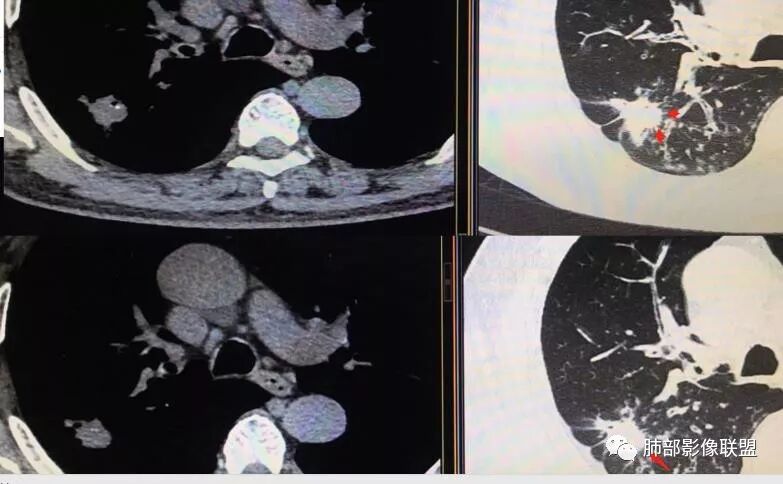

胸CT示病变位于右肺上叶,右肺上叶前段支气管壁不规则增厚狭窄、远端扩张。右肺上叶后段实变影,纵隔窗实变内可见钙化灶,可见支气管引流征,引流支气管壁明显增厚,边缘可见短硬毛刺,胸膜牵拉,u型征,周围可见卫星灶,并可见支气管扩张及其管壁增厚;病灶整体存在膨胀性生长。考虑良性病(结核)变基础上合并癌变,腺癌?

患者中老年男性,咳嗽喘息半年。查体双肺闻及哮鸣音。胸部CT:右肺上叶后段不规则结节灶,可见长毛刺、胸膜牵拉、分叶及钙化征象,周围见点片状卫星灶,近端支气管壁增厚,呈支气管爬行征。综合考虑结核。鉴别恶性病变。

老年男性,咳嗽半年,右肺上叶后段实性结节伴粟粒状卫星灶,结节内有钙化,部分边缘平直,周围见长索条,有胸膜牵拉,结核是明确的,常规需要增强判断有无合并肺癌,当然该患者已经穿刺。

右肺上叶后段结节,点状钙化,边缘见细长毛刺,胸膜凹陷,卫星灶伴树芽症,支气管壁增厚扩张,有截断,考虑结核,但腺癌没法排除,确实有增强就基本能明确。

右肺上叶病灶,可见分叶、毛刺、胸膜牵拉,周围见花花草草,似乎是卫星灶,考虑结核,鉴别腺癌。右肺支气管管壁增厚并扩张,考虑支扩,病史有喘息,哮鸣音,考虑合并有曲霉菌感染。综合考虑腺癌合并结核,曲霉感染。二元。

右肺上叶后段结节,长毛刺、钙化灶、近端小空洞、索条影、周围支气管树丫、引流支气管增厚,主体病灶侧后方分隔样空腔,弥漫支气管增厚,大气道受累,支持感染的征象较多,TB、曲霉;分叶、膨隆、脊状凸起、毛刺等恶性征象也有,遗憾没看到增强,只有期待活检一槌定音。

老年男性,咳嗽半年,右肺上叶后段实性结节,内见钙化,边缘部分膨隆,有长短毛刺、分叶、空泡征,胸膜侧见胸膜牵拉,周围不干净,见小卫星灶,右上叶后段支气管管壁增厚,扩张,有炎性及恶性征象,一元论常规考虑炎性肉芽肿病变,结核可能,腺癌不除外,二元结核并腺癌,建议增强及穿刺活检。

右肺上叶后段占位,毛刺,胸膜凹陷,病灶边缘内可见钙化、空泡,血管进入,病灶周围可见多发粟粒及树芽征,首先考虑肺结核;鉴别腺癌?鳞癌(周围小花、小草?)?

右肺上叶后段团块影,内见钙化,周围胸膜有牵拉,近段支气管扩张管壁增厚,周围可见卫星灶,右支气管狭窄,综合考虑支气管内膜结核,鉴别真菌感染(气道侵袭性曲霉菌病)。

右上后段结节,整体收缩,长软毛刺丶胸膜凹陷,有点状钙化丶小空洞,引流支气管明显管壁增厚,周边卫星灶明显,有喘息史半年,可能有应用激素史,致内源性复发,考虑TB,鉴别腺癌。

右肺上叶后段占位,分叶,毛刺,胸膜凹陷,病灶边缘内可见钙化、空泡,血管进入,病灶周围卫星灶,考虑肺结核合并肺癌。

(右肺肿物穿刺)肺腺癌,贴壁生长型为主,少部分为腺泡型。

3.本例病灶影像表现为:右肺上叶后段不规则结节灶,病灶整体存在膨胀性生长,可见毛刺、胸膜牵拉、分叶及钙化征象,近心端小空洞,周围见点片状卫星灶并出现磨玻璃影,近端支气管壁增厚,管腔扩张,既有恶性征象,也有结核的征象。南边老师考虑结核与腺癌同时存在,但遗憾的是缺乏增强扫描图像,亦未提供结核相关辅助检查结果。